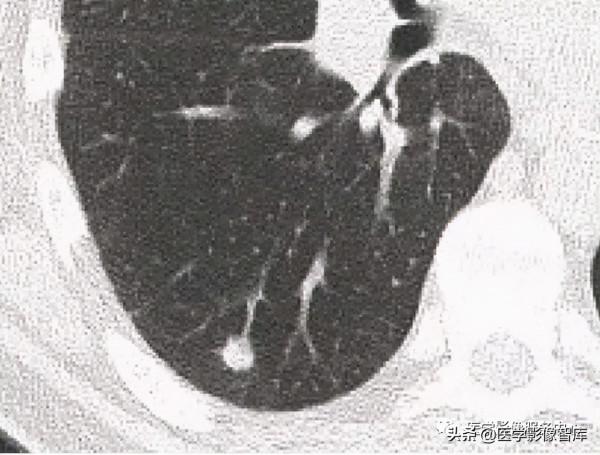

圖19. 陽性⽀⽓管徵 A和B均可⻅⽀⽓管⽓道通向腫塊,⽀⽓管鏡活檢為⾮⼩細胞肺癌

陽性⽀⽓管徵:胸部CT表現為直接通向周圍肺結節或腫塊的⽀⽓管⽓道(圖19A, 19B)。 這是預測經⽀⽓管肺活檢和⽀⽓管內超聲刷洗是否成功的有⼒線索。Gaeta等⼈報道,第四級⽀⽓管⽔平以上發現陽性⽀⽓管徵時,經⽀⽓管活檢和刷洗的成功率為90%。